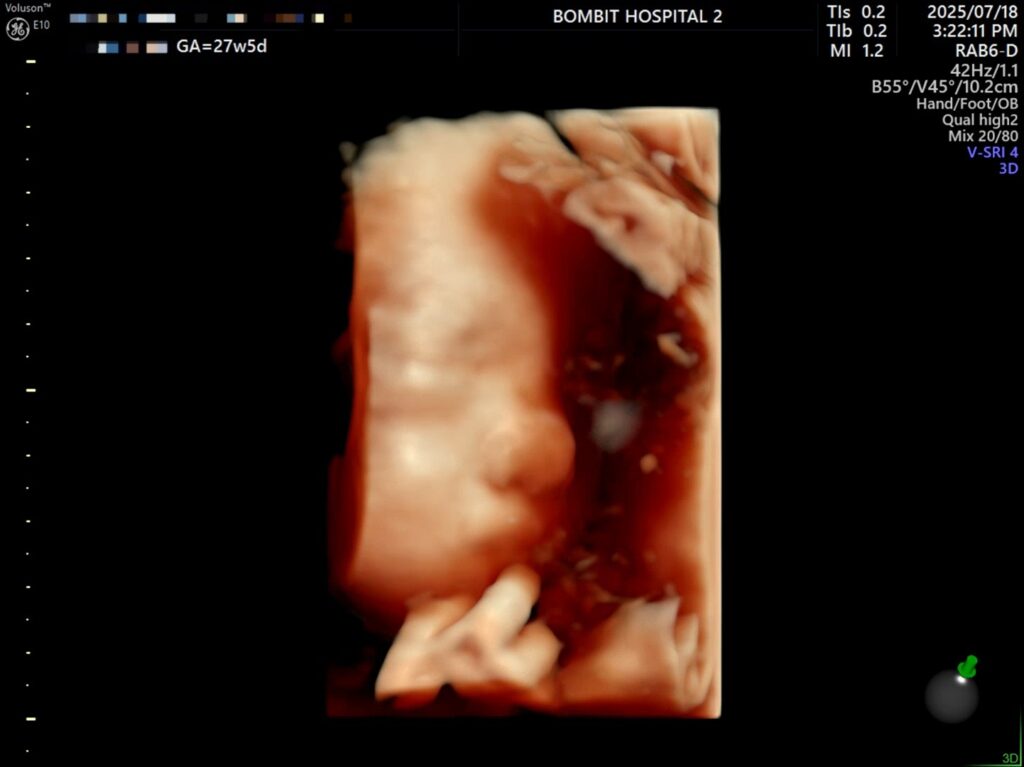

입체초음파로 본 단비는 처음에 완전히 엎드려있었다. 바닥을 향해 엎드려서 얼굴을 파묻고 귀 밖에 안 보여줌.. ㅜㅜ

– 처음에 보여준 귀.. 귀욥